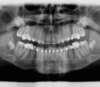

Panoramique